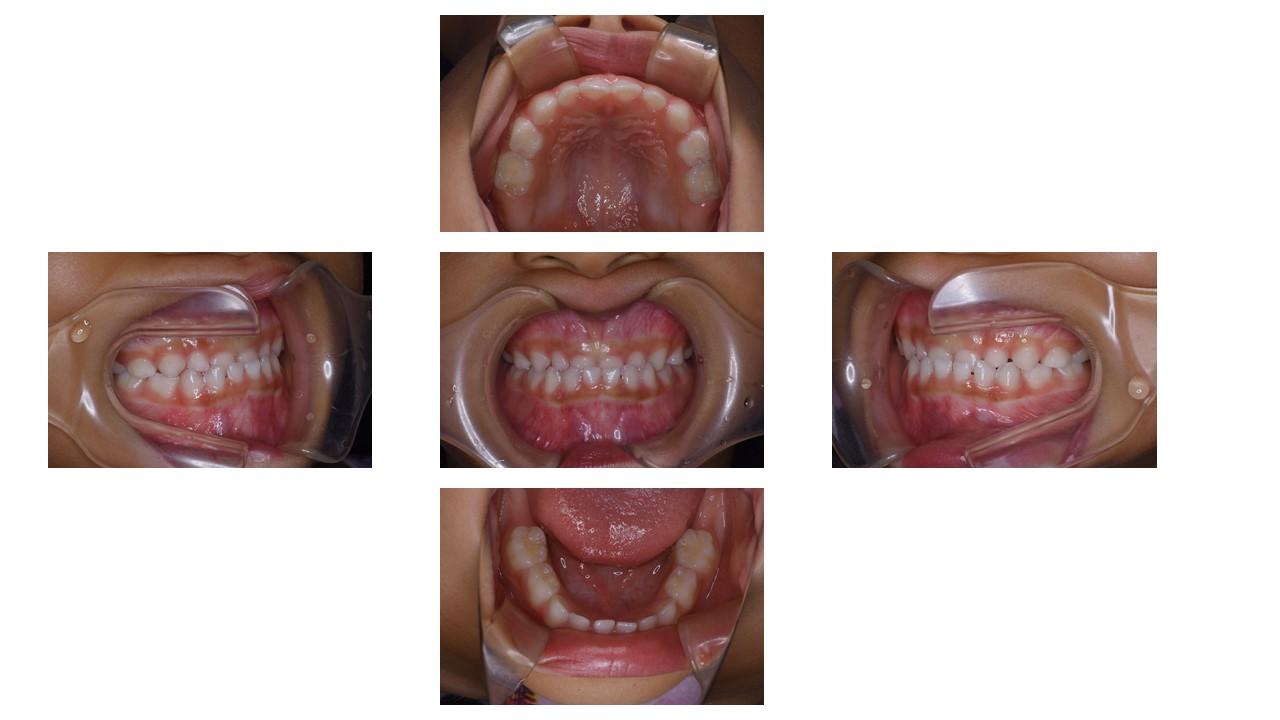

「叢生」は、一般的に「乱ぐい歯(らんぐいば)」「八重歯(やえば)」「ガタガタの歯並び」などと呼ばれる状態で、日本人に非常によく見られる不正咬合(ふせいこうごう:良くない噛み合わせ)です。

<叢生の状態>

顎(あご)の骨の大きさに対して、歯のサイズが大きすぎたり、歯が並ぶスペースが不足していたりするために、歯がデコボコに重なり合って生えている状態を指します。